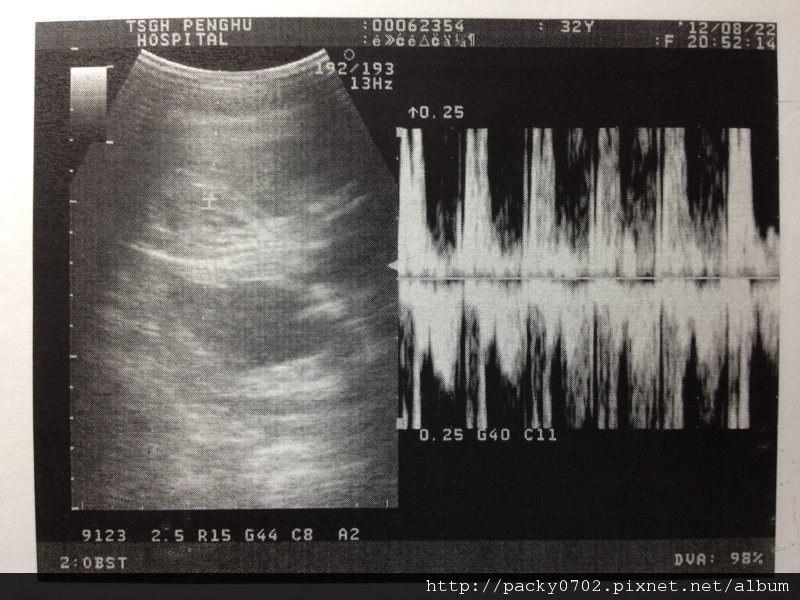

先聽聽小子的心跳,噗通噗通很有精神~

20120822 (2)